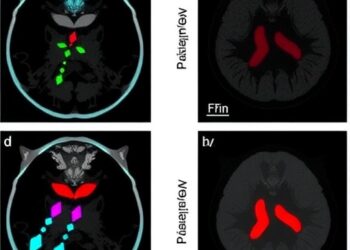

In a groundbreaking advancement poised to reshape the future of Parkinson’s disease treatments, researchers have meticulously charted the intricate developmental ...